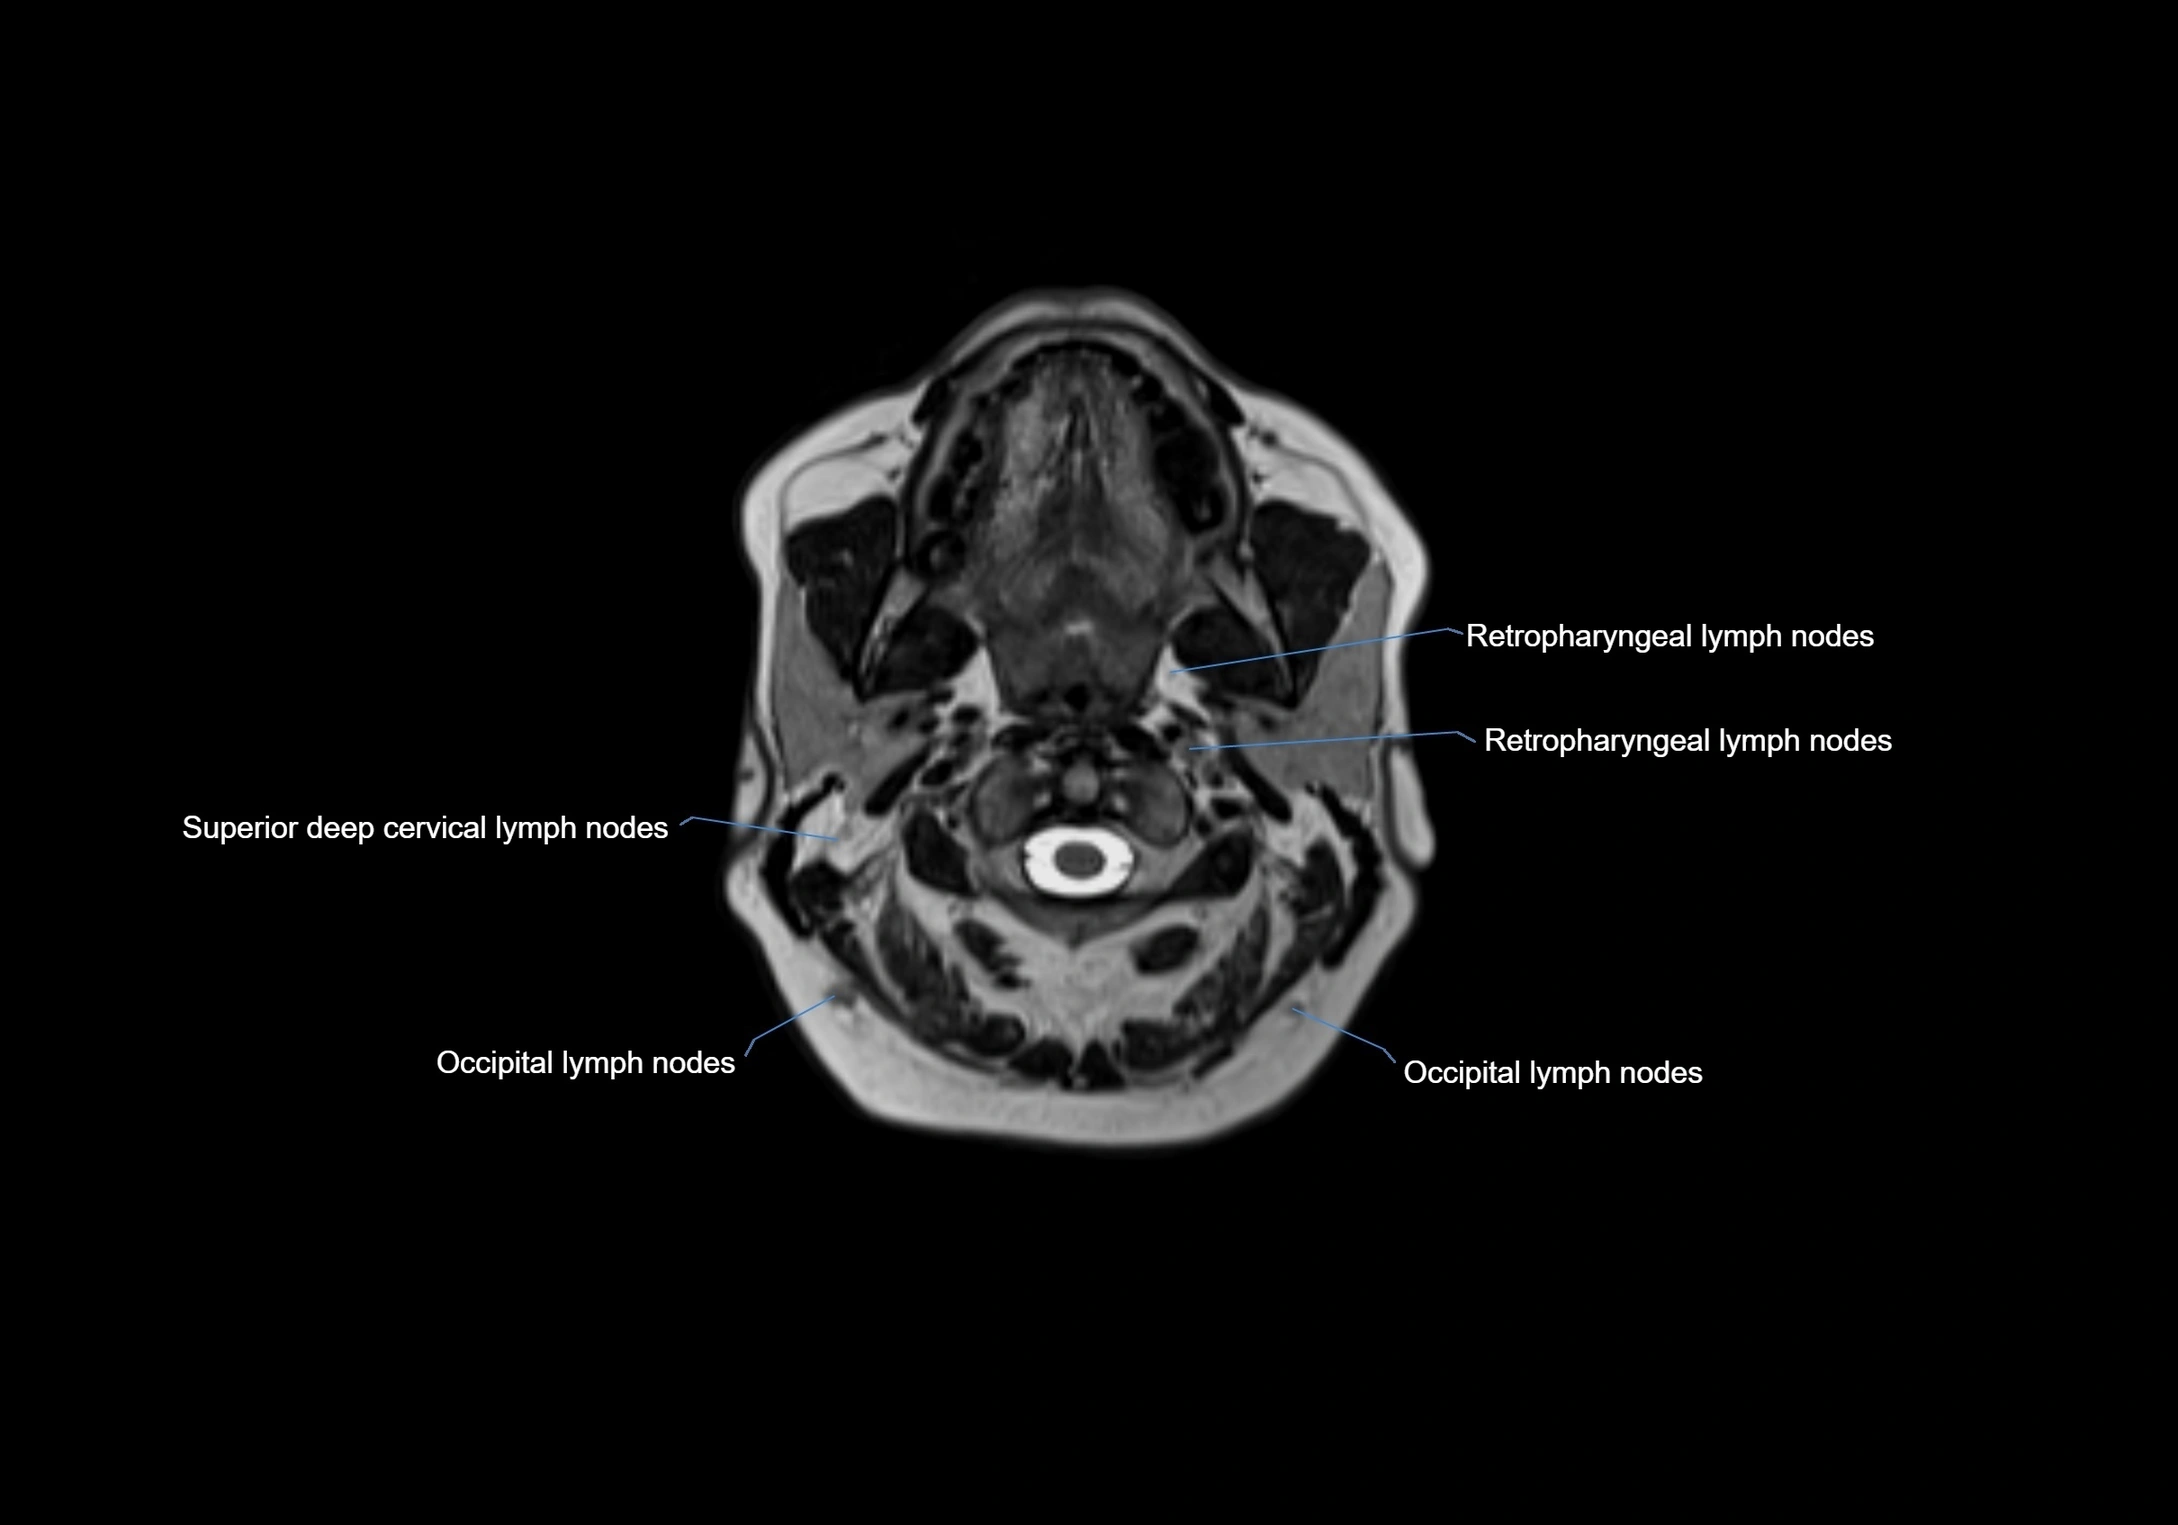

Location

• Found along primary lymph node chains, including preauricular, submandibular, parotid, and occipital regions

• Embedded in subcutaneous fat or superficial fascia, often lateral or posterior to primary nodes

• Variable in number; may occur unilaterally or bilaterally, depending on individual anatomy

MRI images

image